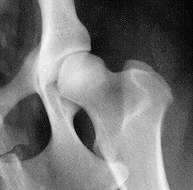

normale Hüfte